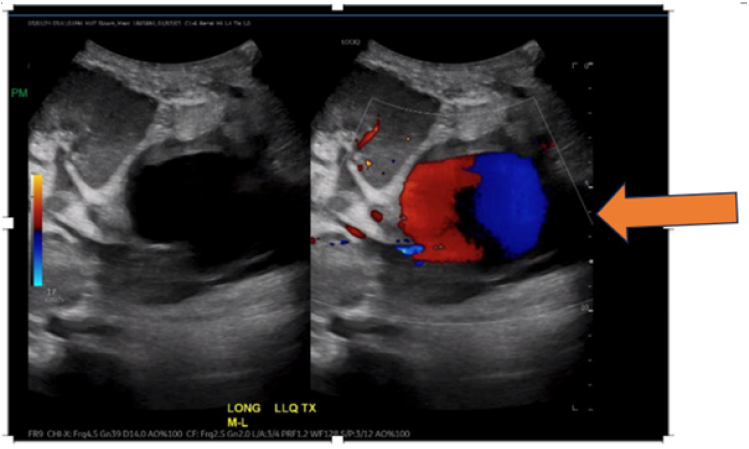

Due to consistent pain at the Left lower quadrant, CT abdomen and pelvis was obtained that revealed a heterogenous mass just inferior to the transplant kidney measuring an estimated 7x5.7cm (Figure 1). An ultrasound of the transplanted kidney revealed a large Pseudoaneurysm (PSA) in the deep iliac fossa just inferior to the graft (Figure 2).

Figure 2: doppler US transplant kidney: thick-walled round fluid collection in the deep iliac fossa inferior to the graft measuring 6cm in diameter with internal arterialized waveform with yin-yang morphology, consistent with pseudoaneurysm.